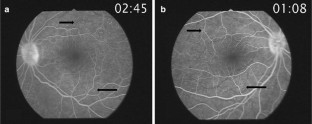

Vogt-Koyanagi-Harada (VKH) disease is a systemic disease consisting of bilateral granulomatous panuveitis combined with cutaneous and neurologic manifestations. However, there have been few reports of brain magnetic resonance imaging (MRI) in VKH disease. A 54-year-old Korean woman presented with severe periorbital pain, blurred vision and meningismus. Ophthalmologic examination disclosed bilateral optic disc edema with peripapillary nerve fiber hemorrhages. Lumbar puncture revealed monocytic pleocytosis. After a diagnosis of VKH disease was made, the patient was treated with high-dose corticosteroid. Brain MRI showed diffusely thickened posterior ocular walls with retinal detachment and perineural infiltrative changes along the optic nerves and adjacent pachymeningeal enhancement of the anterior temporal lobes bilaterally. We report a case of VKH disease with panuveitis and meningeal involvement of the anterior temporal lobe detected by brain MRI.

Fig. 1

Fig. 2

Fig. 3